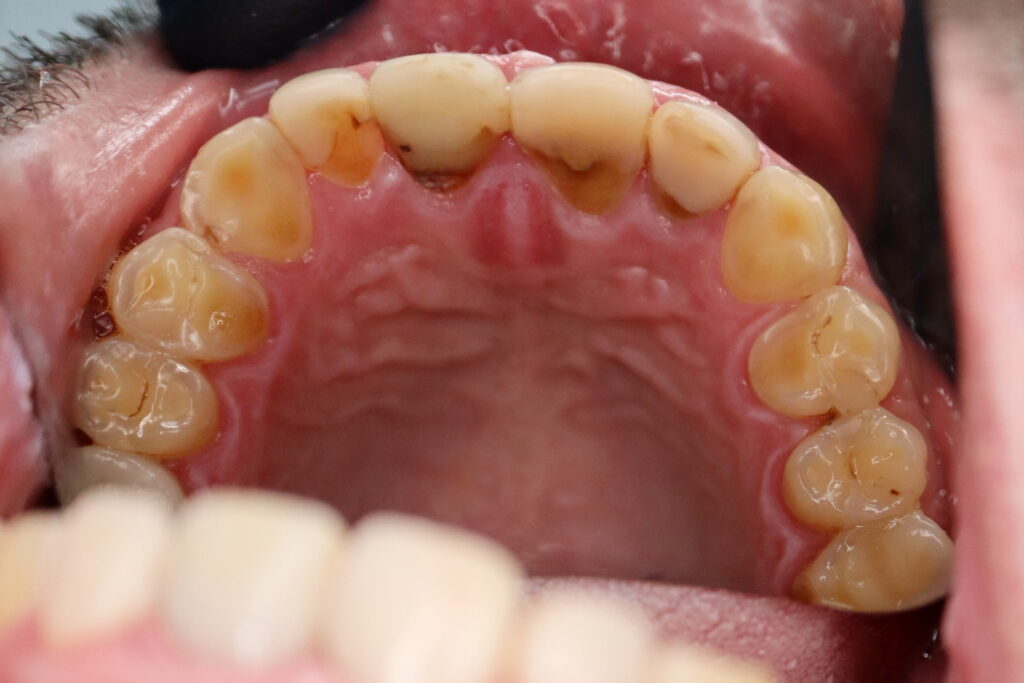

Результаты

Стоимость всего комплекса: 870 USD (цена указана ориентировочно по курсу НБРБ на день оплаты)

результат имплантации